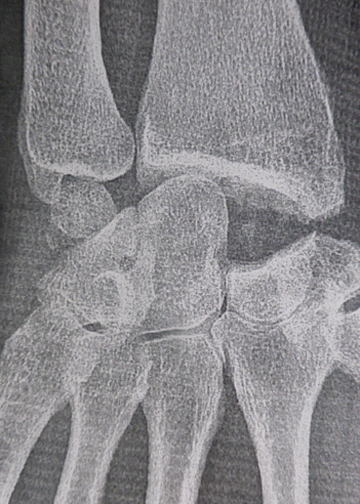

Arthrodèse des 4 os internes:

Le scaphoïde a été enlevé.

Les autres os du carpe sont fusionnés avec les vis.